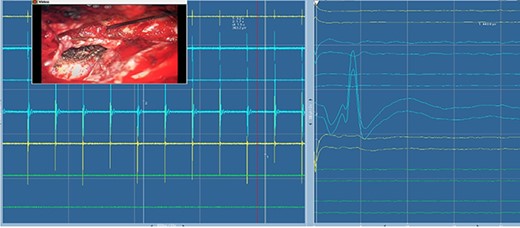

Mapping the margins using monopolar stimulation revealed no positive responses, and therefore we preceded to incise the tumor capsule and partially debulk the lesion. Frozen section suggested histology consistent with HPC. The foramen ovale was widened and the tumor was removed from that area as well. The integrity of the all divisions of the trigeminal nerve were continuously monitored throughout via somatosensory evoked potential (SSEP) recordings from scalp electrodes, and via direct nerve stimulation of the sensory and motor branches, and blink reflex monitoring (Figs 3–6). All monitoring modalities were replicable and stable throughout tumor removal. The dura over the temporal lobe was then opened. The tumor was identified and extensively debulked with a ultrasonic aspirator (SonopetR, Stryker, Michigan USA). The capsule was dissected from the left temporal lobe and the whole intradural component was removed. The foramen ovale and the trigeminal nerve were observed from the intradural space (Fig. 2g).

Electromyography of trigeminal nerve (motor). Trigger EMG of the motor branches of the trigeminal nerve with positive motor responses (mentalis muscle EMG). Nearby cranial nerves were additionally monitored including the facial nerve CN VII (orbicularis oculi, orbicularis oris and mentalis muscle) and abducens nerve CN IV (lateral rectus muscle).

Direct nerve stimulation of the sensory V2. Direct nerve stimulation of the sensory branch V2 at the foramen ovale demonstrating cortical SSEPs recorded from scalp electrodes (montages C4’-Cz’, C4’-Fz, C4’-C3’) accordingly to the international 10–20 EEG system. Average latency: 5.4 ms, amplitude: 12.5 μV.

Trigeminal V2 SSEP recordings. Trigeminal V2 SSEPs were continuously recorded on the scalp using the montage C4’-Fz. Average latency: 5.4 ms, amplitude: 13 μV.

Blink reflex. Blink reflex from left side stimulation of the supraorbital branch of the trigeminal nerve was observed with EMG activity from left orbicularis oculi muscle. Both early response (R1) and late reflex activity (R2) were recorded throughout the surgical procedure.